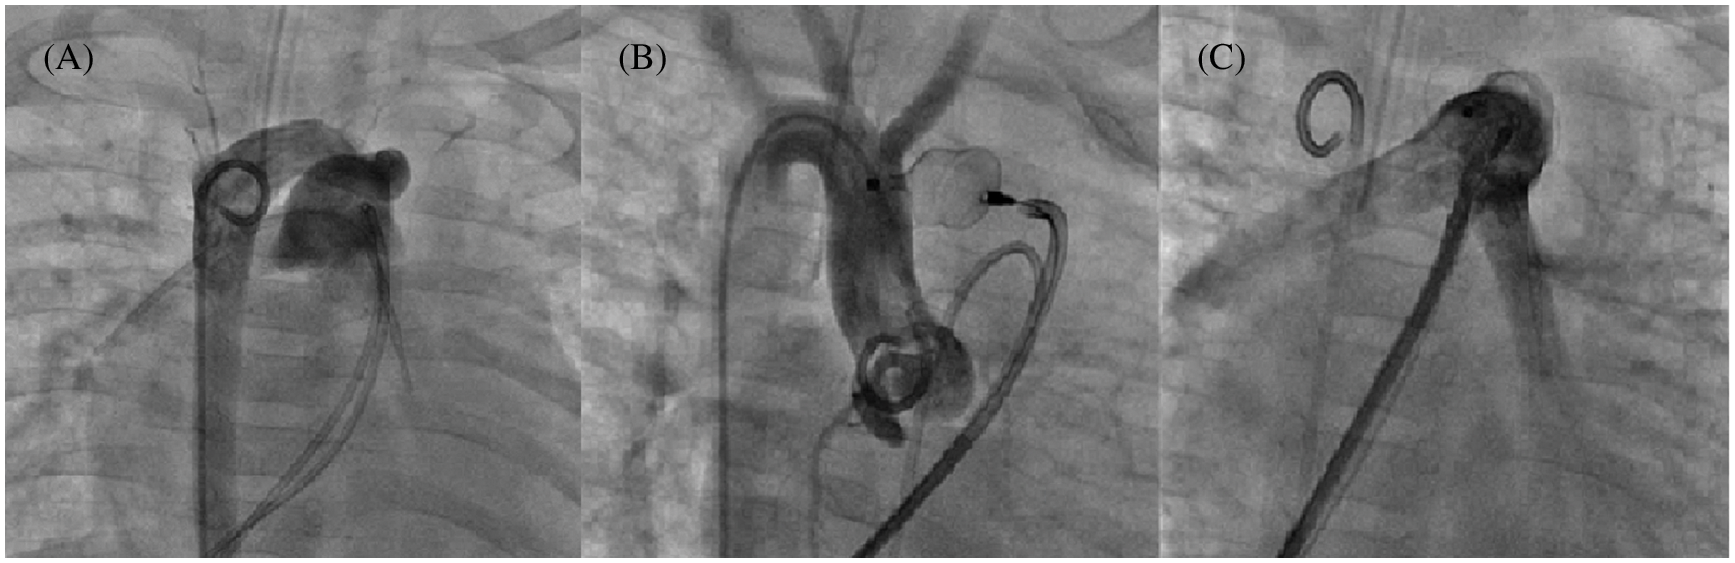

Overall, 55 PDA occlusions were performed with a minimal diameter of 5.5 ± 1.6 mm and different morphologies [22]: 47.3% type C (tubular morphology, Fig. 4), 7.3% type A, 21.8% type D, 3.6% type D/E, and 20% type E.

Figure 4: Tubular PDA closure using a 12 mm AVP II in a 6 kg infant. Multiple angiograms. (A): 7.6 mm tubular PDA with a right sided aortic arch; (B): AVP II deployment into the PDA without shunt; (C): Absence of pulmonary artery stenosis before device release